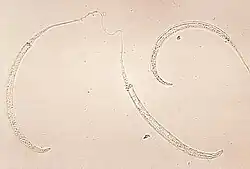

Гельминтозы, передающиеся через почву

Гельминтоз, передающийся через почву, является наиболее распространенным забытым тропическим заболеванием[67].Три основных вида червей, ответственных за гельминтозы, передаваемые через почву, — это Ascaris (круглые черви), Trichuris (власоглав), анкилостомы Necator americanus и Ancylostoma duodenale, а также Strongyloides stercoralis[68]. В настоящее время инфицировано 1,5 миллиарда человек[68]. Геминтоз, передаваемый через почву, встречается в странах Африки к югу от Сахары, Северной и Южной Америке, Китае и Восточной Азии[68]. Риск смертности очень низок[16] .Наиболее распространенными симптомами являются анемия, задержка роста, проблемы с кишечником, недостаток энергии и нарушение физического и когнитивного развития[16][68]. Инфицированные дети часто отстают в учёбе[16]. Тяжесть симптомов зависит от количества червей в организме[68].

Паразитические черви обычно передаются через зараженные человеческие фекалии и почву, которые распространяются в окружающей среде, например, из-за открытой дефекации[68]. Наиболее распространенным методом лечения является медикаментозное лечение[68]. Его можно предотвратить с помощью гигиенически приготовленной пищи и чистой воды, улучшенных санитарных условий, периодической дегельминтизации и санитарного просвещения[68]. Всемирная организация здравоохранения рекомендует массовую дегельминтизацию без предварительной диагностики[68].